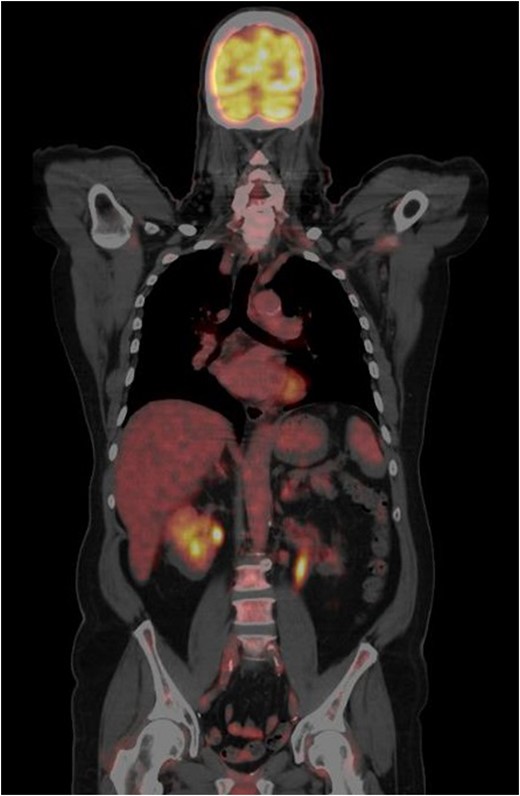

CT-PET done one year from the previous CT-PET. This showed complete remission of disease. No evidence of distant metastatic disease.